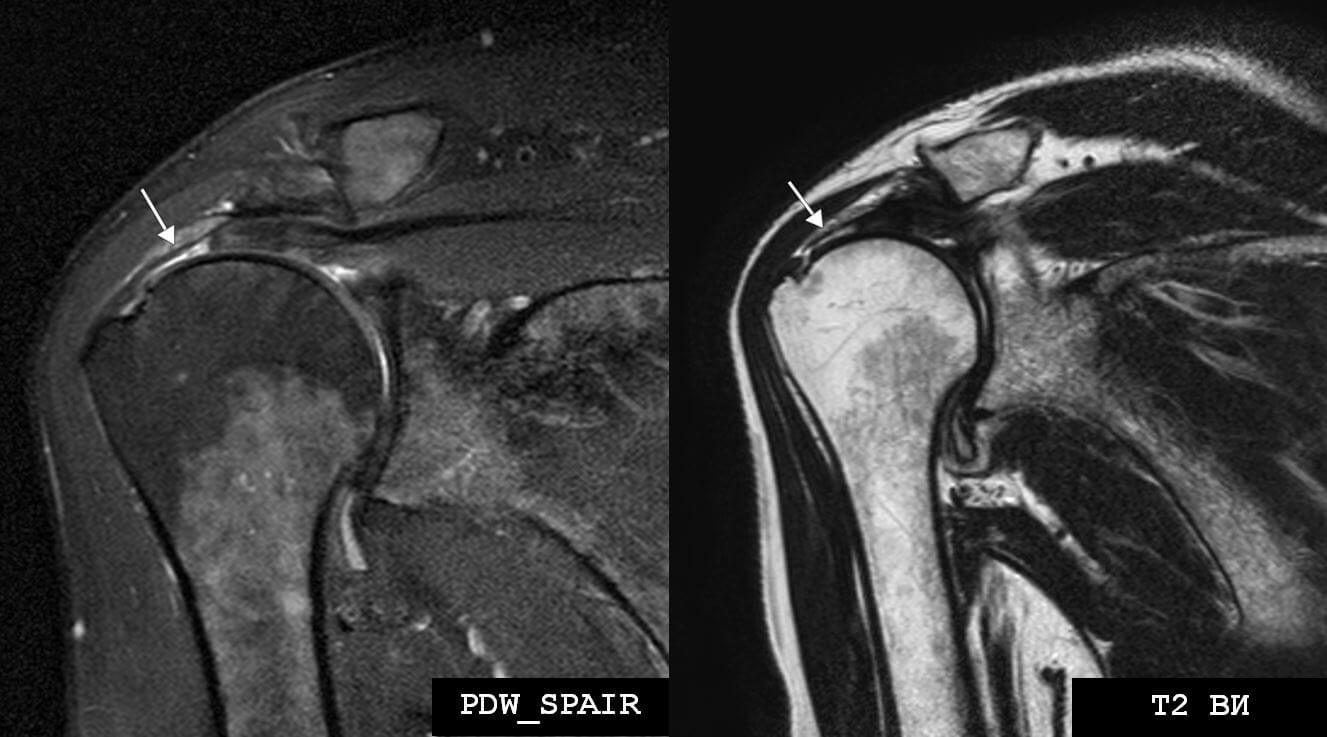

Повреждение мышц мрт

Повреждение мышц мрт 88 фото